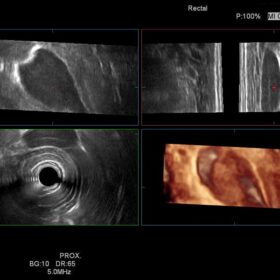

Ultrasound HI VISION Ascendus – Image Gallery and Videos

Obstetrics 4D mode and Urology